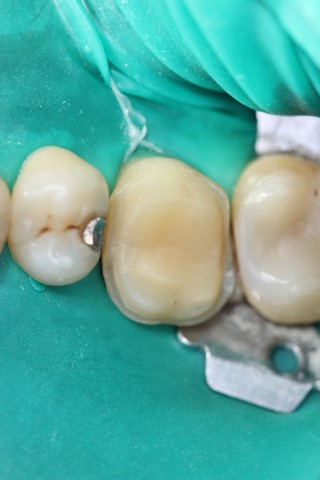

Gli intarsi dentali vengono proposti quando abbiamo ancora tessuto dentale sufficiente ad evitare una corona, ma troppo esiguo per procedere ad una semplice otturazione.

Il dente per essere recuperato viene sottoposto ad una particolare preparazione, successivamente alla quale si rileva un’impronta con materiali specifici (polieteri) ed inviata al laboratorio odontotecnico dove a seconda dei casi si decide alla realizzazione dell’intarsio in ceramica, di-silicato o composito.